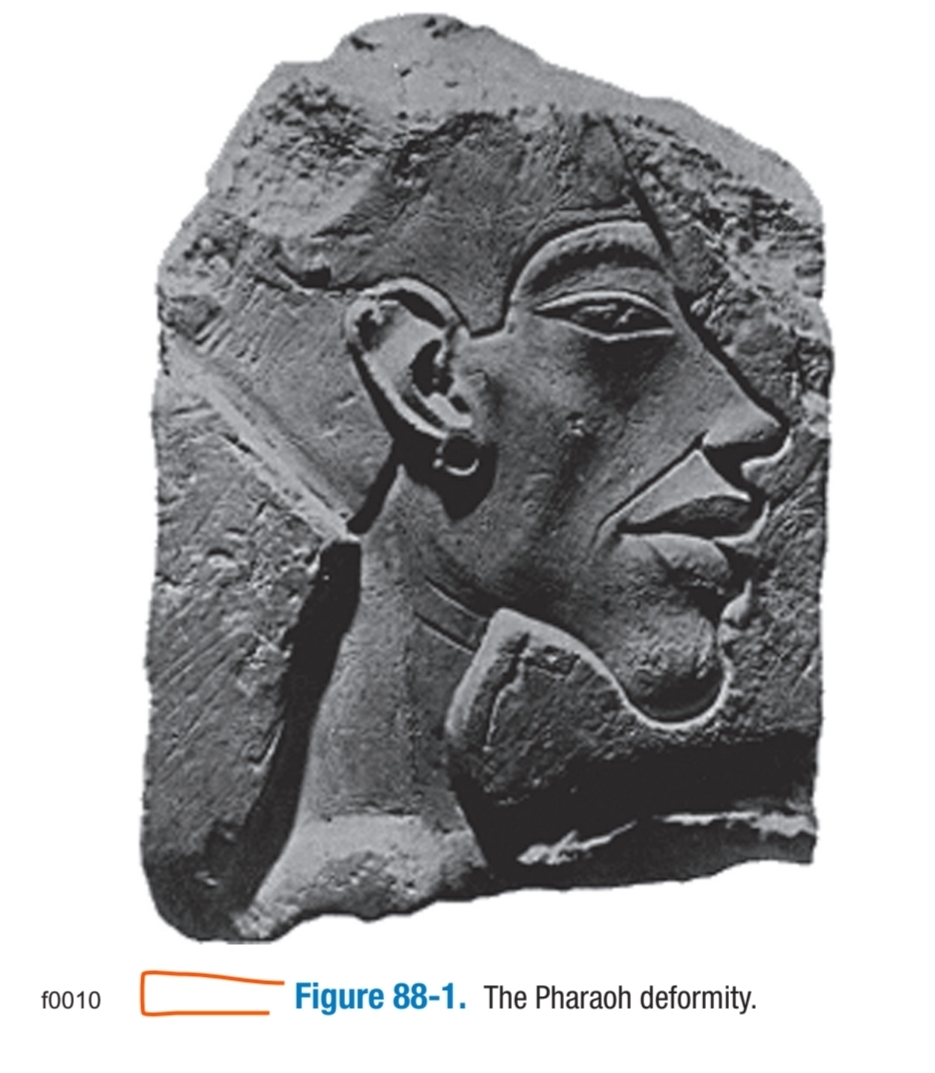

View attachment 4843627

Nothing here indicates it can avoid Pharaoh's chin or reduce the step off

If you look at the diagram provided you can literally only go Anteriorly or Posteriorly rotation would cause a crazy step off - even worse than a genioplasty step off